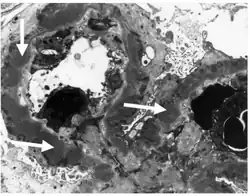

Subepithelial dense deposits and basement membrane reaction arrows

Subepithelial dense deposits and basement membrane reaction arrows Immune complexes (black) are deposited in a thickened basement membrane creating a "spike and dome" appearance on electron microscopy.

Immune complexes (black) are deposited in a thickened basement membrane creating a "spike and dome" appearance on electron microscopy.

- On electron microscopy, subepithelial deposits that nestle against the glomerular basement membrane seems to be the cause of the thickening. Also, the podocytes lose their foot processes. As the disease progresses, the deposits will eventually be cleared, leaving cavities in the basement membrane. These cavities will later be filled with basement membrane-like material, and if the disease continues even further, the glomeruli will become sclerosed and finally hyalinized.